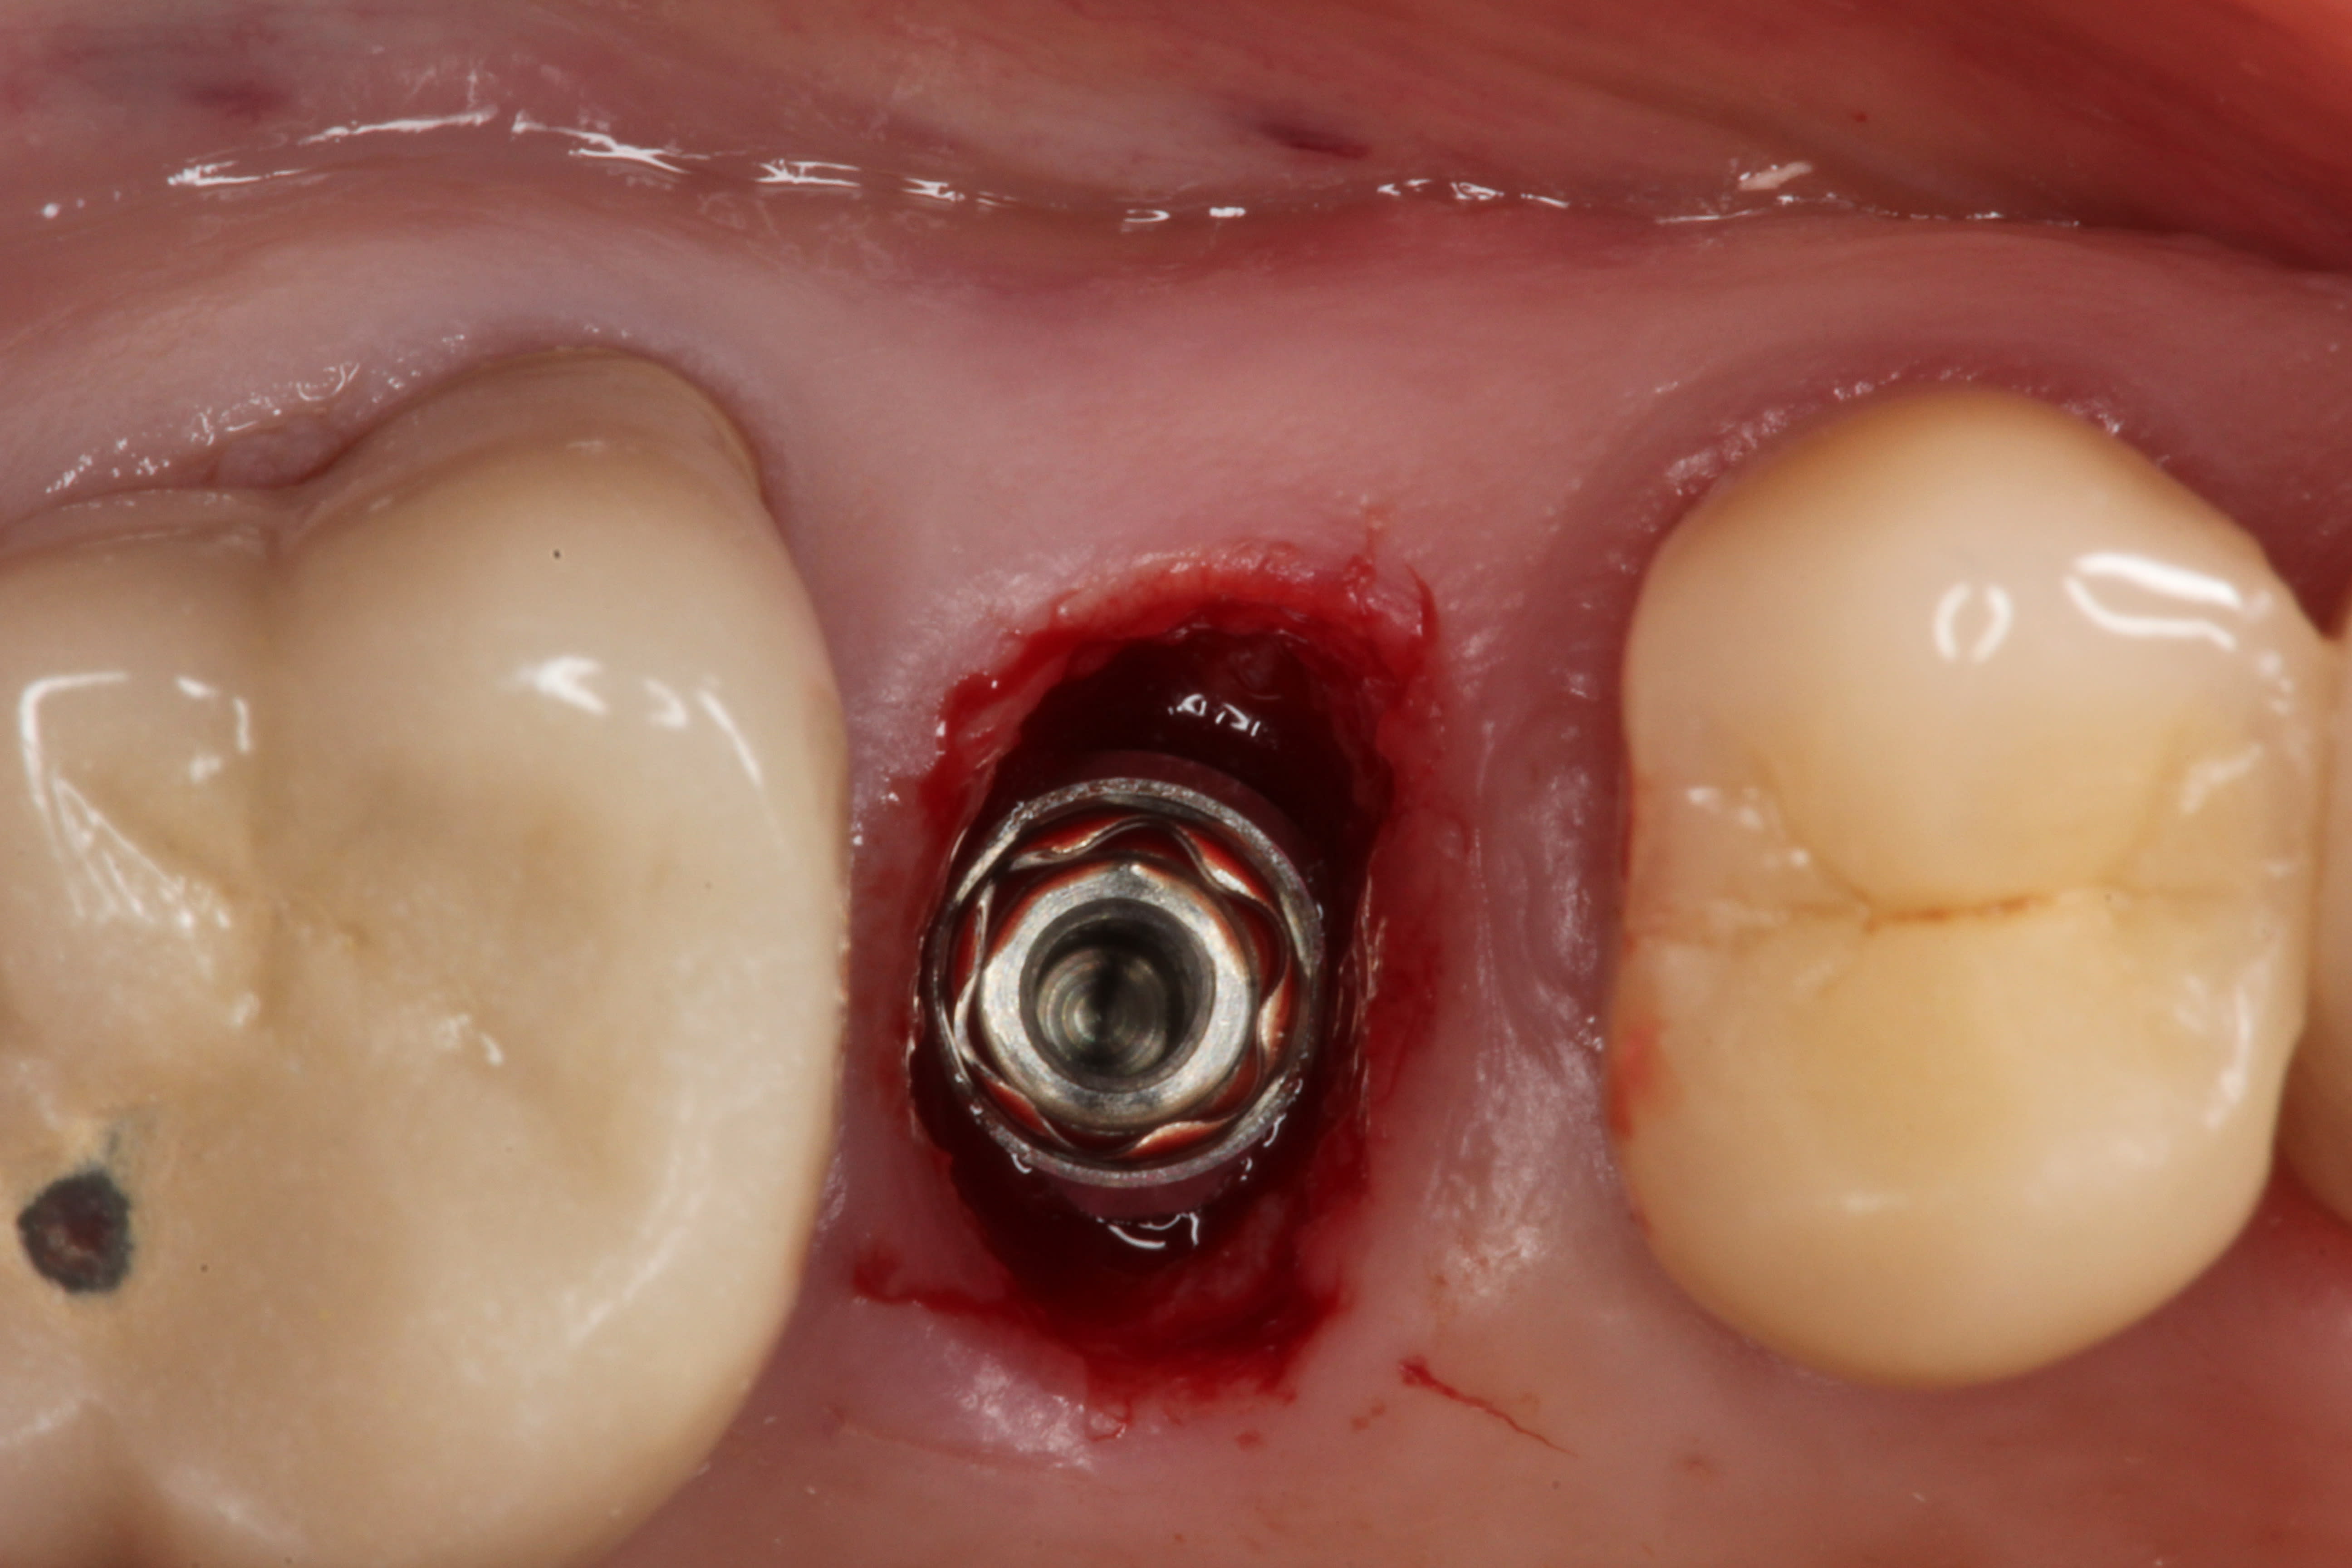

Accordingly, the patient enrolled in the multicenter study in December 2011. She opted for extraction, immediate provisionalization, and immediate loading, and visited both the oral surgeon (JMA) and prosthodontist (MAP) authors’ practices on the same day in January 2012 to consolidate these phases. Teeth Nos. 8 and 9 were extracted under local anesthesia (infiltration with lidocaine 2% with 1:100,000 epinephrine, 3.6 mL). The crowns were removed, then the roots were elevated and extracted. Osteotomy was made in type II (moderate) bone with Class A bone quality; all socket walls were intact. After tapping the sites, two 4.5-mm x 13-mm tapered implants (Genesis) were placed with primary stability of 40 Ncm (Figure 21) and 5-mm healing covers were placed (Figure 22 and Figure 23). The buccal socket gaps were grafted with spongious bone substitute (Bio-Oss®, Geistlich Pharma North America, www.geistlich-na.com). The gingival margins were reapproximated with 4-0 chromic sutures. Postoperative radiographs confirmed proper positioning in the alveolar bone.

Immediately after surgery, the prosthodontist attached prefabricated polymethylmethacrylate (PMMA, tooth-colored) provisional abutments (Temporary Abutment®, Keystone Dental, Inc) with screws. The abutments were hand-tightened and minimally prepared with a diamond bur. Laboratory-fabricated splinted provisional crowns were relined with Jet Acrylic (Lang Dental Manufacturing Co, Inc, www.langdental.com), adjusted, and cemented with eugenol-free zinc-oxide temporary cement (RelyX™ Temp NE, 3M ESPE) on the PMMA temporary abutments. Teflon was used to seal the access holes. The patient was instructed to minimize chewing on these teeth and restrict hard food for 6 weeks.